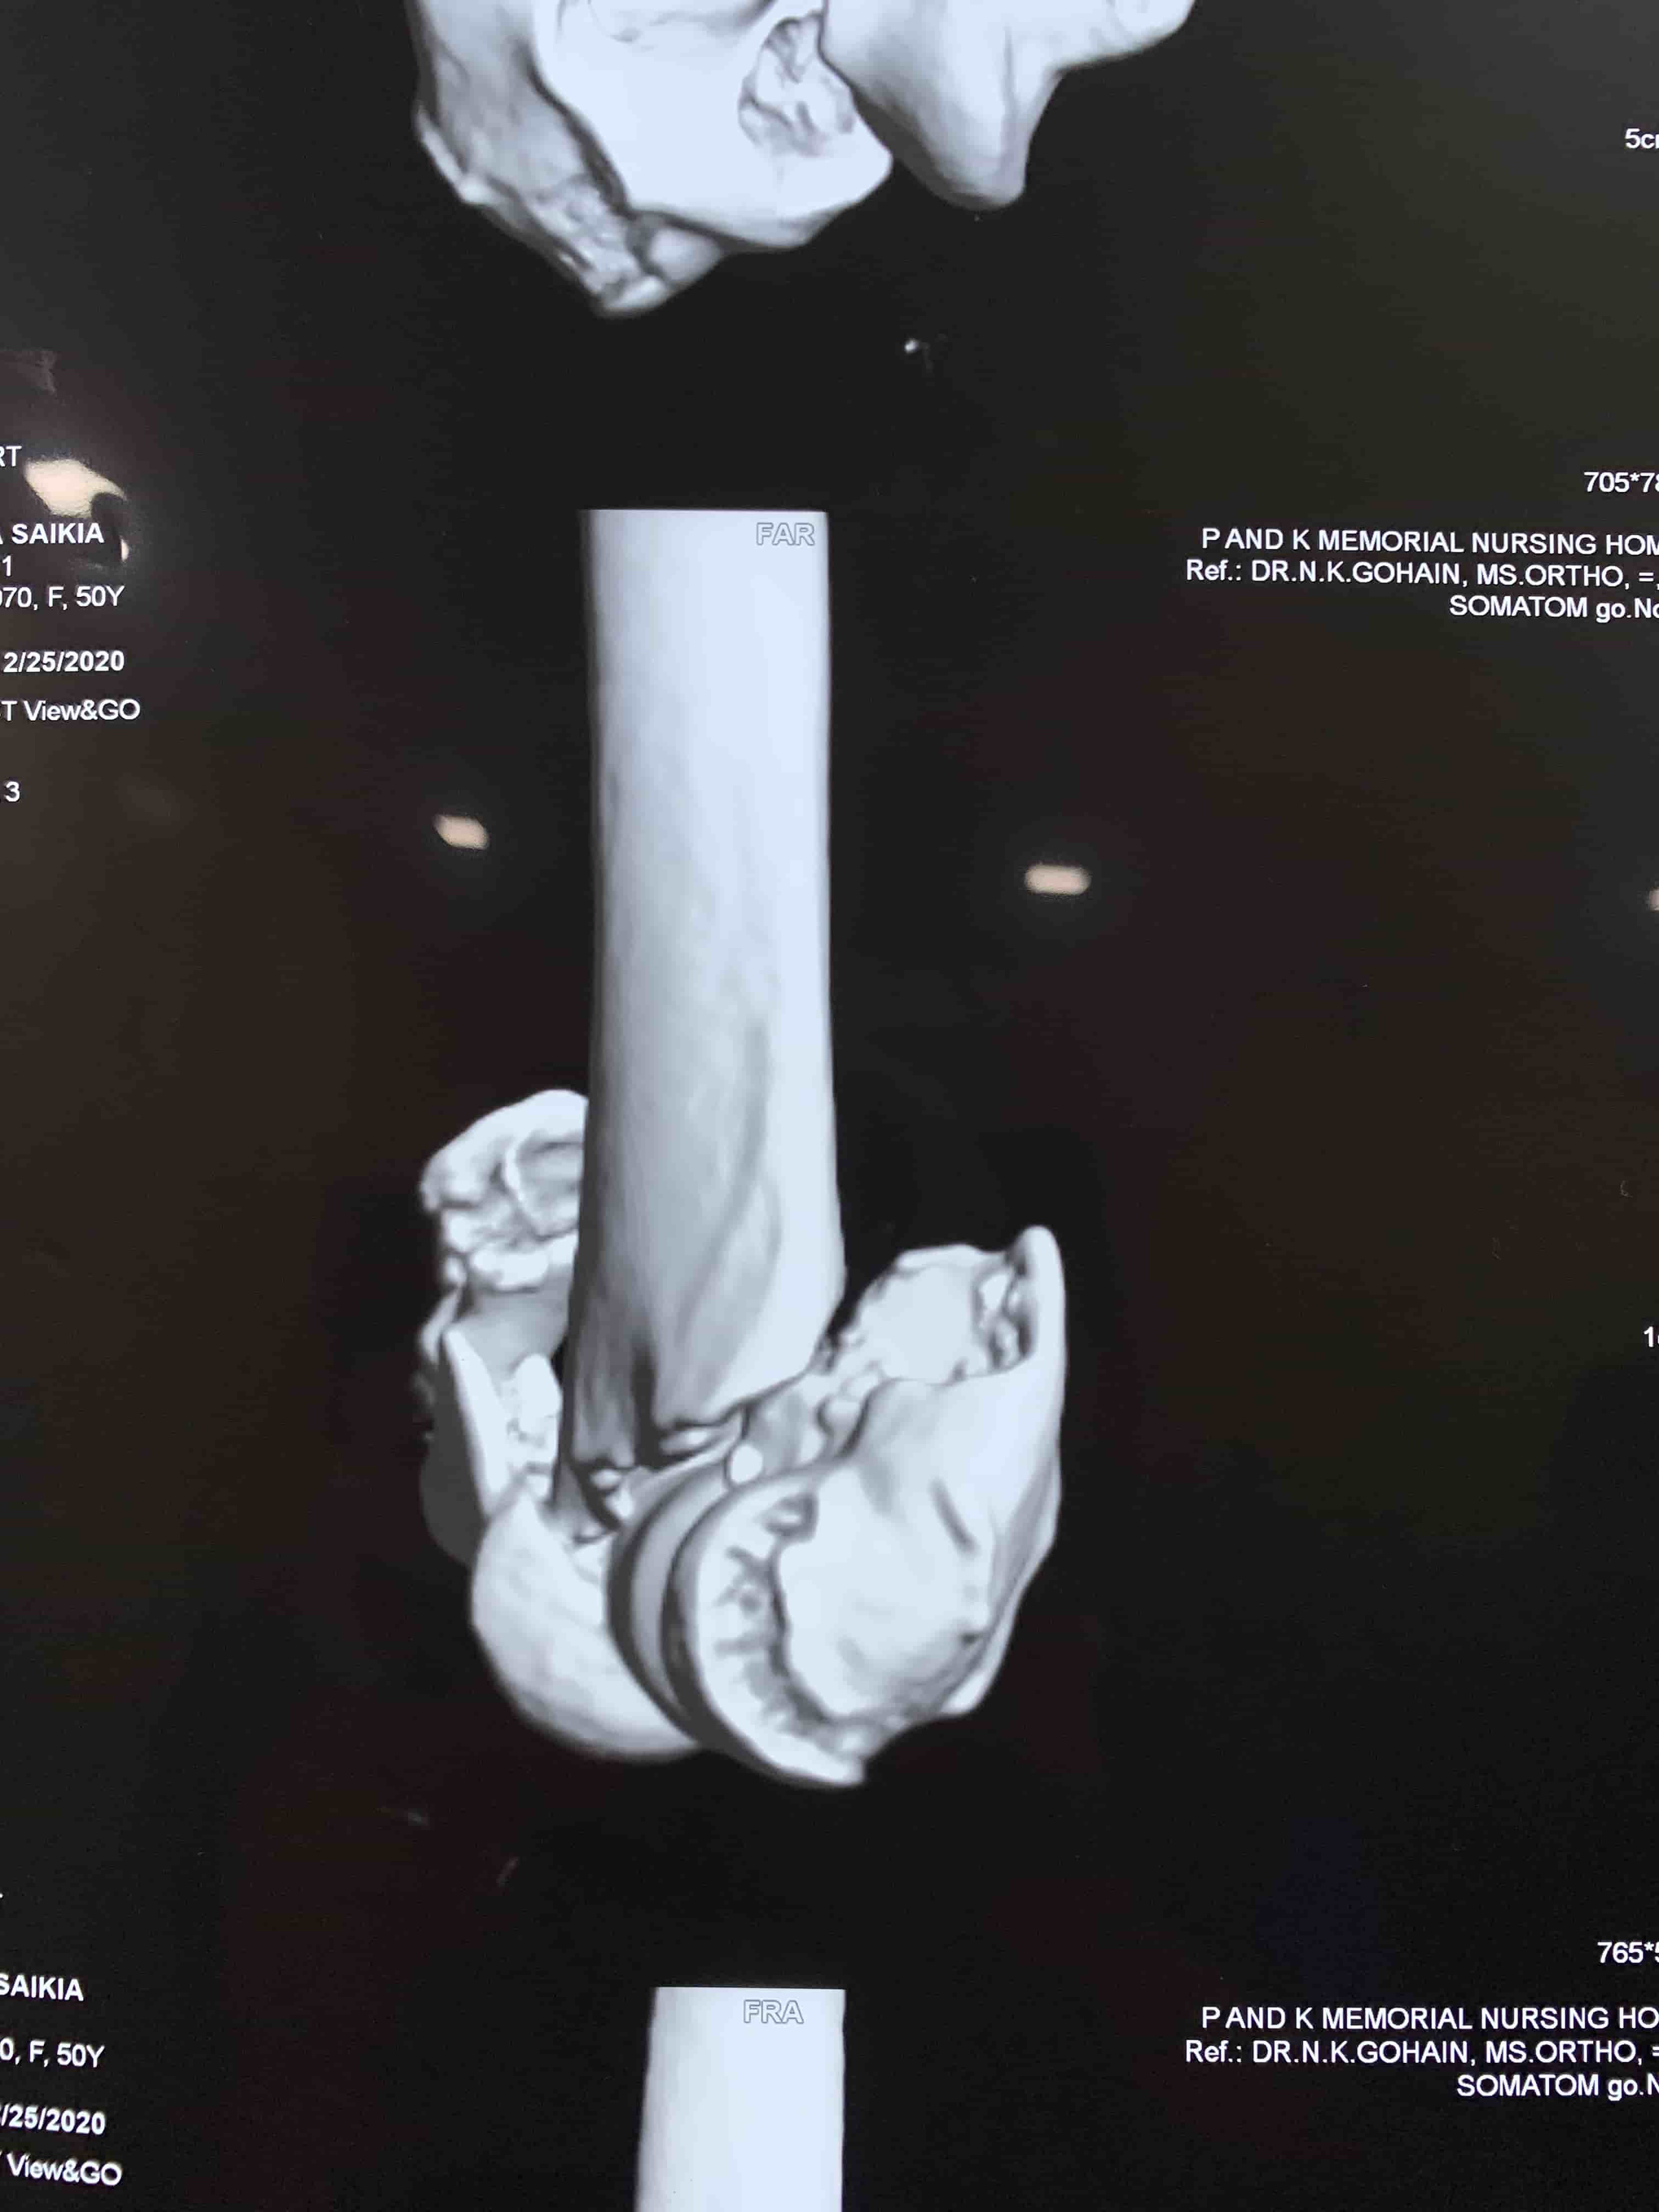

Complex Distal Humerus Comminuted Fracture

Complex Distal Humerus Comminuted Fracture

Complex Distal Humerus Comminuted Fracture

Complex Distal Humerus Comminuted Fracture

Complex Distal Humerus Comminuted Fracture

Complex Distal Humerus Comminuted Fracture

Complex Distal Humerus Comminuted Fracture

Complex Distal Humerus Comminuted Fracture

Complex Distal Humerus Comminuted Fracture

Complex Distal Humerus Comminuted Fracture

Complex Distal Humerus Comminuted Fracture

Complex Distal Humerus Comminuted Fracture

Complex Distal Humerus Comminuted Fracture

Complex Distal Humerus Comminuted Fracture